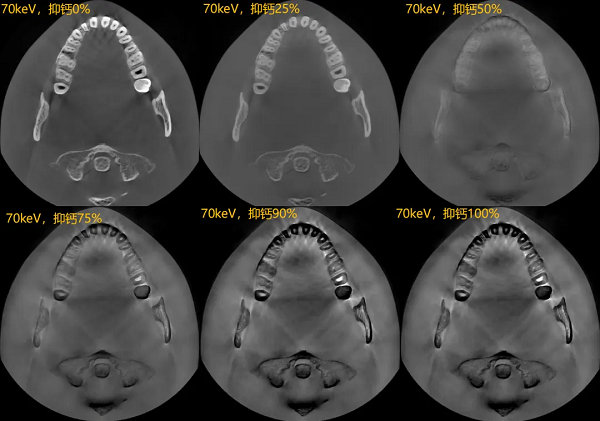

双能技术被称为传统成像的颠覆性技术,其不仅能实现对组织伪影的有效去除,更能特异性地对组织进行特殊处理,如去钙图/有效原子序数图等。

去钙图:双能技术可以有效识别骨质中的钙成分,并特异性地对钙成分进行抑制,而且这种抑制可以进行不同程度的调节;对于受骨钙成分影响较大的骨髓显影,有着优异的临床效果。